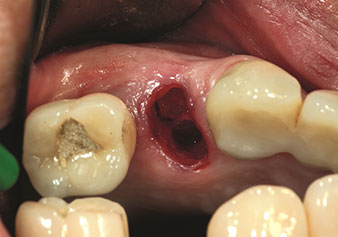

Gestion alvéolaire

Une application souvent sous-estimée est l’extraction atraumatique de racines dentaires ou de fragments radiculaires dans le cadre d’une gestion alvéolaire. Les périotomes à denture fine, qui sont actuellement disponibles en deux versions (EX1 et EX2 de W&H), peuvent également être utilisés pour extraire facilement des dents qui ont subi un traitement endodontique spécifique préalable ou des racines ankylosées. On obtient des alvéoles d’extraction dans lesquelles à la fois les tissus durs et les tissus mous sont entièrement préservés.

Ceci instaure des conditions optimales pour un traitement implantaire ultérieur ou immédiat (Figures 1 et 2 fournies avec l'autorisation du Dr Torsten Conrad, Bingen

am Rhein).

Fig. 1 : Périotome à denture fine (insert EX1). Photo : © Dr Torsten Conrad (Bingen am Rhein)